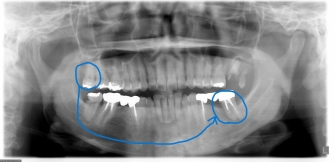

◎左写真 初診時、移植前の写真

右上の親知らずを、左下の第二大臼歯(歯牙破折のため抜歯になったため)に移植する外科処置を行いました。